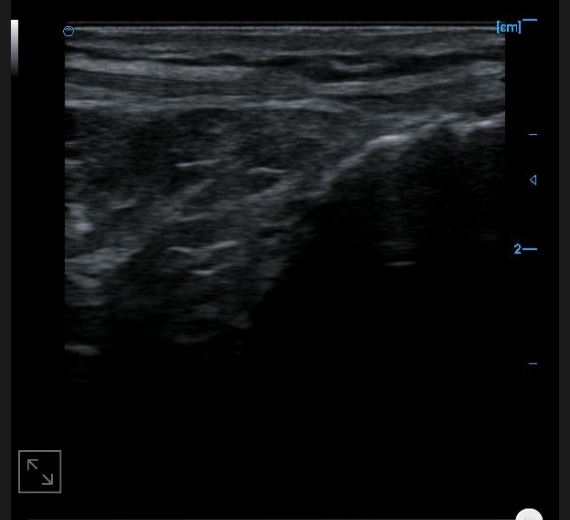

Knee collateral ligament B image